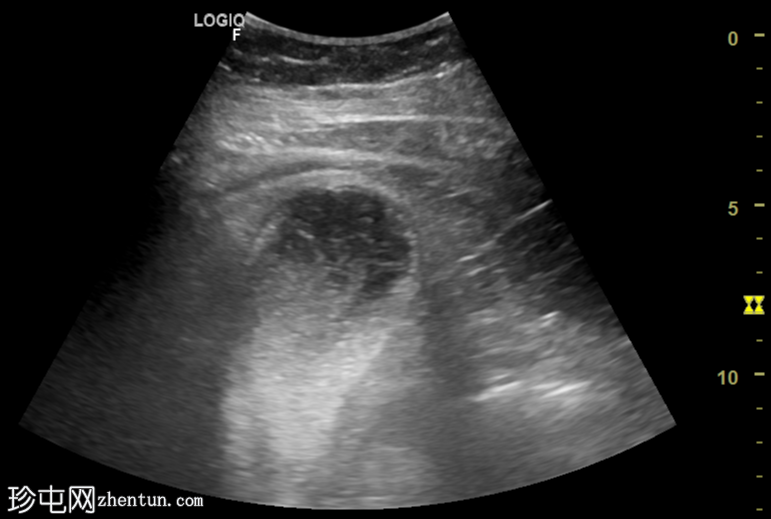

纵切面

胆囊扩张,充满回声不均的异质性高回声物质(高回声、等回声、低回声),并可见漂浮回声。

可见胆囊周围水肿,胆囊壁不对称增厚,呈局灶性断裂,胆囊壁内可见强回声灶和强回声线(可能为气体腔)。

总体表现提示复杂性胆囊炎(坏疽性)。